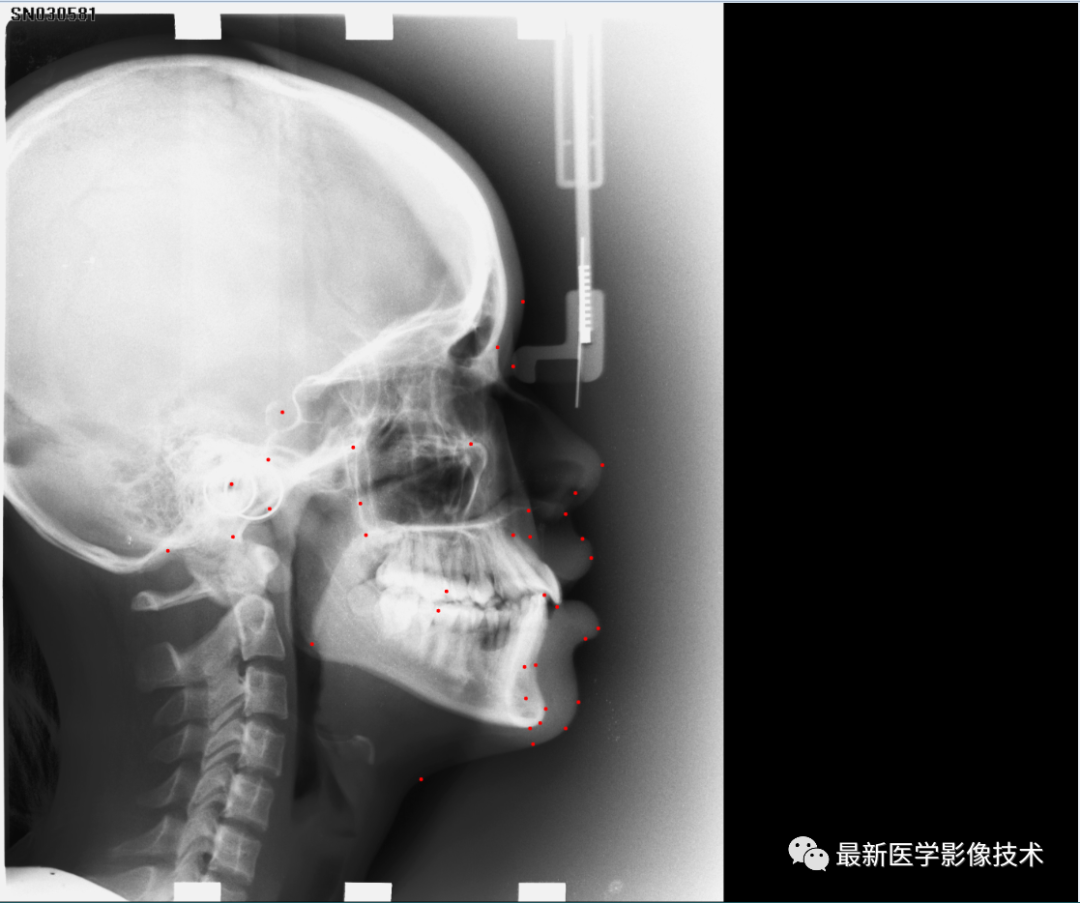

1、头颅非零区域提取,去除图像0像素填充区域,得到ROI图像。

2、将ROI图像缩放到固定大小512x512,对ROI图像采用均值为0,方差为1的方式进行归一化处理。关键点坐标按照图像比例缩放到512x512的尺度,然后将38个关键点坐标生成38个通道的高斯热力图,高斯sigma参数是10,然后将数据分成训练集和验证集。

3、搭建VNet2d和Unet2d网络,使用AdamW优化器,学习率是0.001,batchsize是4,epoch是100,损失函数采用focal loss和L2。

5、验证集检测结果

2个Unet2d+Vnet2d结果

其中在512x512分辨率下,vnet结果的MRE是6.1,unet结果的MRE是5.2,unet+vnet+unetls结果的MRE是4.27,单位是1个像素。